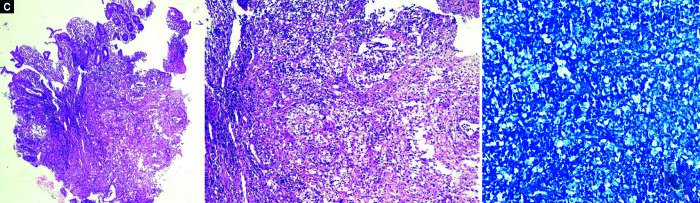

肠热病是东南亚地区的常见病,表现形式多种多样。部分治疗往往会导致病程延长。此外,肠道造影往往会与肺结核相混淆。结肠镜检查和活组织检查有助于与肺结核相鉴别。有关肠热病结肠镜检查的资料很少,而且大多来自胃肠道(GI)出血的病例报告。我们描述了三例肠道热伴有胃肠道受累的病例,其症状与肺结核相似。结肠镜检查的特征是回肠粘膜呈粉蓝色,水肿,扩张性减弱,并伴有多处浅表溃疡。所有三个病例的回盲瓣均受累。两个病例累及升结肠。治疗后随访发现病灶完全消退:Verma A, Dahale AS, Gopal P, et al.模仿科赫氏病的无并发症肠炎结肠镜检查结果。Euroasian J Hepato-Gastroenterol 2024;14(1):120-123.

Enteric fever is a common occurrence in Southeast Asia with a myriad of presentations. Partial treatment often leads to prolonged illness. Along with this, bowel imaging often confounds the picture with tuberculosis. Colonoscopy and biopsy may help to differentiate from tuberculosis. The data on colonoscopy is scarce in enteric fever and is mostly available from case reports of gastrointestinal (GI) bleeding. We have described three cases of enteric fever with GI involvement mimicking tuberculosis. The colonoscopy picture is characteristic of pinkish-bluish ileal mucosa, with edema and decreased distensibility, along with multiple superficial ulcers. The ileocecal valve was involved in all three cases. The ascending colon was involved in two cases. There was complete resolution of lesions after treatment on follow-up.